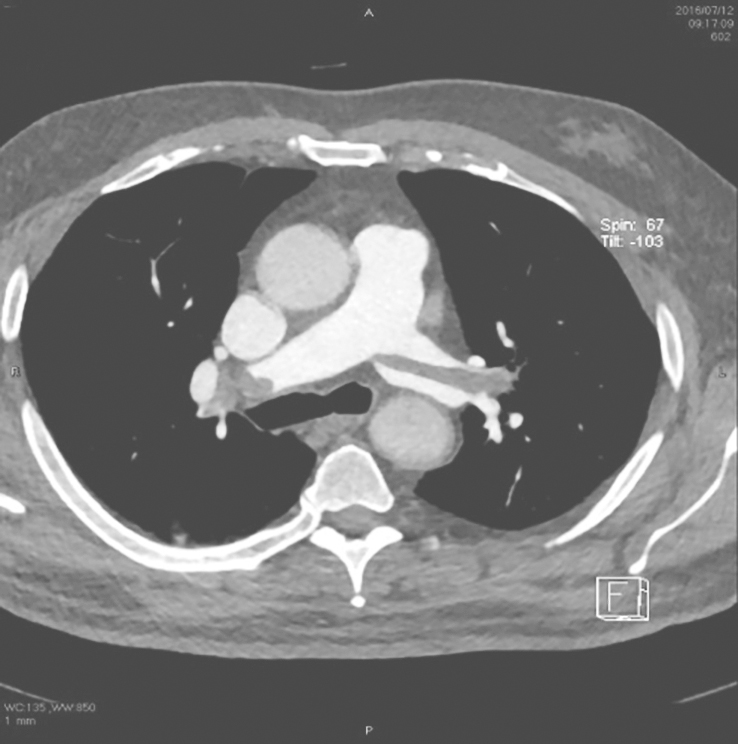

入院后给予达肝素钠2500U、每12小时1次,抗凝治疗。CTPA检查示,肺动脉分叉处、左右肺动脉内可见较大条状低密度充盈缺损,较大条状低密度影大小约8mm×56mm。右上肺动脉、右下肺动脉、左上肺动脉、左下肺动脉各段动脉内也可见多发低密度充盈缺损(图1)。双下肢静脉超声示,右下肢肌浅静脉末端、小腿肌间静脉陈旧性血栓。

图1CTPA可见左、右肺动脉低密度充盈缺损